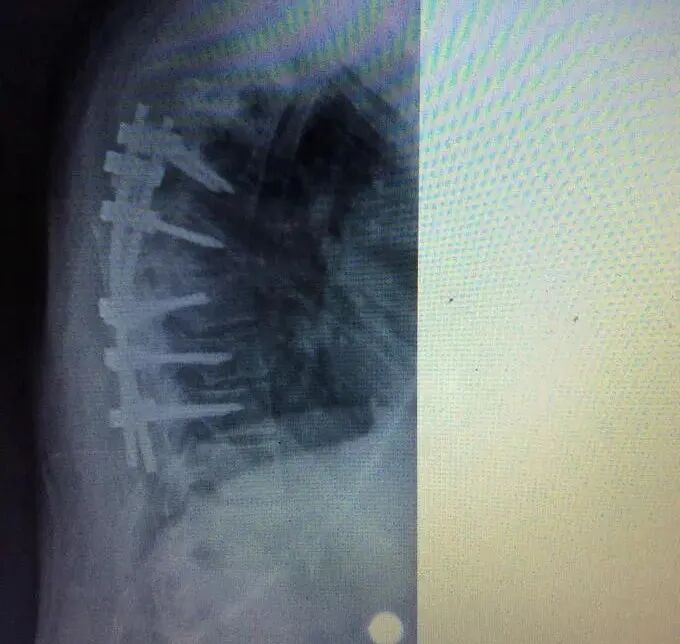

胸椎结核和其他脊柱结核一样易发于椎体,以破坏脊柱的前柱、中柱为主。而且,又因其本身存在的生理性后凸,应力集中在椎体的前侧, 患者负重后容易造成椎体塌陷,从而就导致后凸畸形十分的明显。结核杆菌喜欢生长在血液丰富的地方,人的脊椎椎体以松质骨为主。它的滋养动脉为终末动脉,静脉血流到这里速度缓慢,结核杆菌容易停留在椎体部位。于是,胸椎结核在各方面因素的影响下就产生了。 本期专家推荐